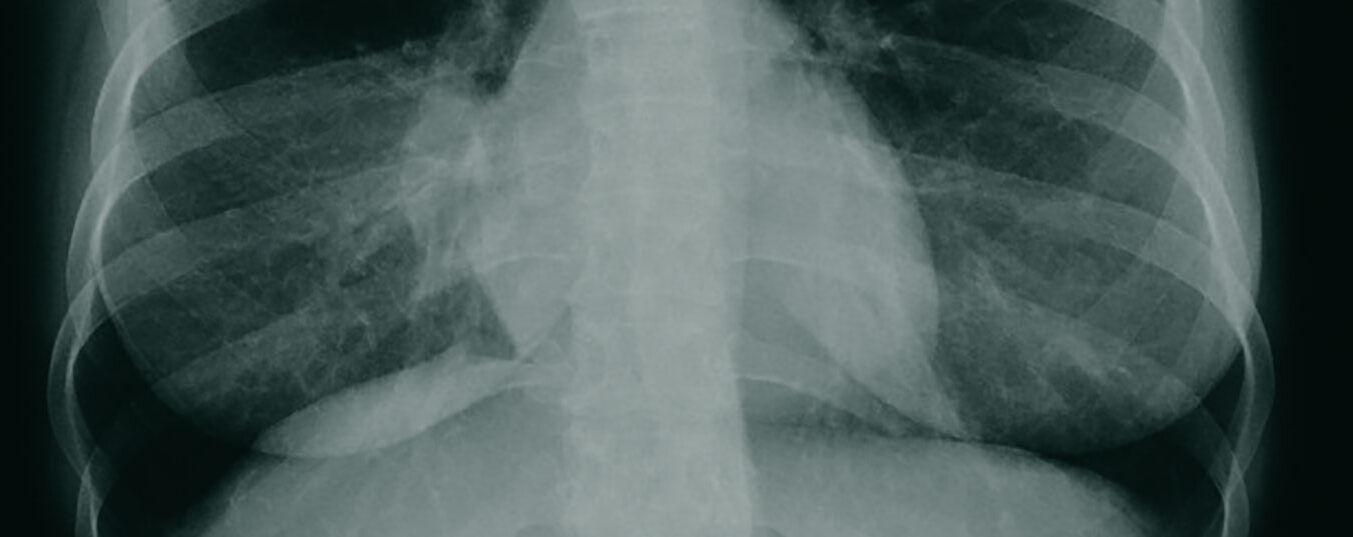

Carcinoma polmonare – Tumore di Pancoast

Il carcinoma polmonare è uno dei tumori maligni più comuni nei Paesi di lingua tedesca. L’età media di insorgenza è tra i 68-70 anni. Il principale fattore di rischio è il fumo. Henry Pancoast (1875-1939), un radiologo americano, diede il suo nome a un carcinoma bronchiale periferico particolarmente localizzato. Oggi, il successo del trattamento dipende, tra l’altro, dallo stato iniziale dei linfonodi e dal raggiungimento di una resezione R0.